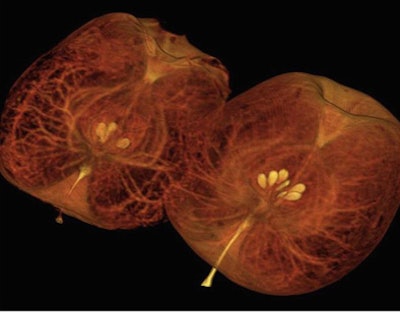

During a live demonstration that included scanning acorn squashes and watermelons for the benefit of a reporter, the staff compared images from CT750 HD side-by-side with the older GE model, revealing finer resolution of internal structures in the former.

- The Gemstone detector, which leverages the superior light-handling properties of garnets; in imaging applications, the detector supports material decomposition for the entire 50-cm field-of-view